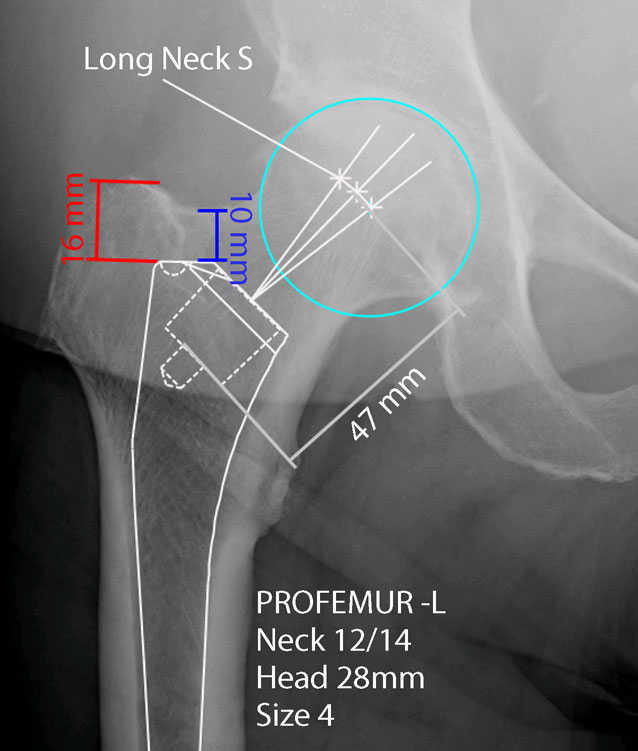

术前进行必要的术前规划